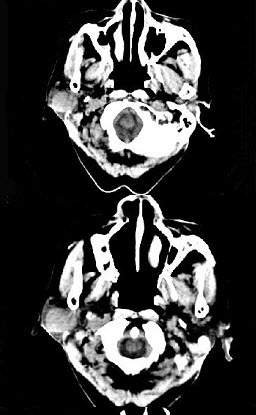

女,72岁,六年前于右面颊部扪及一包块,缓慢增大,其表面较光滑,CT如图所示,该病例应诊断为()。

A、Worthin瘤

B、腮腺混合瘤

C、颈部神经纤维瘤

D、颈部淋巴瘤

E、小唾液腺瘤

B